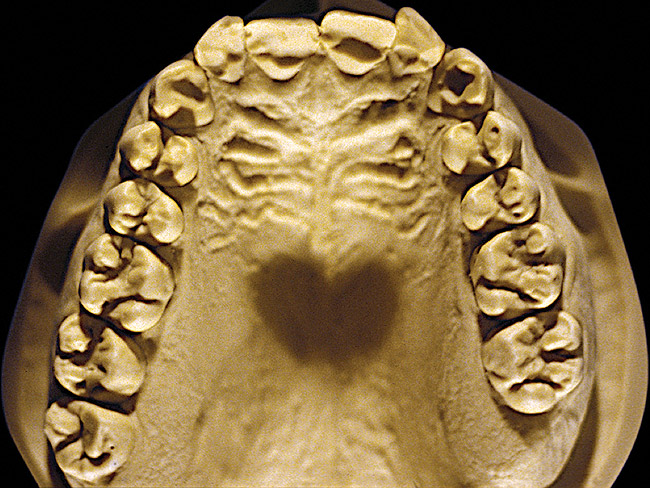

Figure 4  Advanced NCLTS from bruxism, maxillary arch.

Figure 4

The patient shown in Figure 3 and Figure 4 exhibited severe NCLTS from bruxism. Examination of the casts indicated that the NCLTS was progressively greater toward the anterior teeth. Cupping and cratering was not present because there was no secondary cause. Figure 5 and Figure 6 detail another bruxism patient, but to a lesser degree and one with cupping/cratering caused by toothpaste. The cups or craters were not caused from bruxism because the teeth could not touch the bottom of the invaginations. In both featured patients, upon hand-articulating the casts, the NCLTS facets matched up and the diagnosis of bruxism was confirmed.